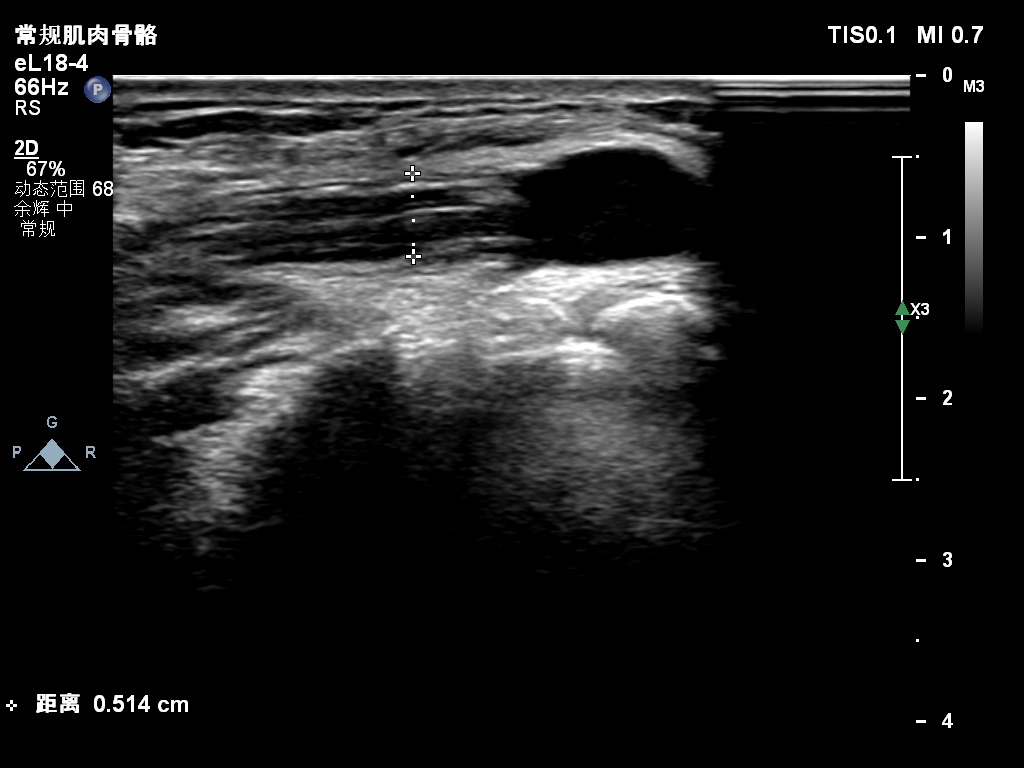

超声所见:右侧尺神经于肘管上段增粗,较粗处横截面积约0.25cm²,神经外膜及神经束膜显示欠清晰,神经纤维连续性可。尺神经走行至肘管处受压变扁,局部尺神经外膜处可见囊性结构并向肘管远段延伸,边界清,形态不规则,内可见多条带状分隔。CDFI:囊性结构内未见明显血流信号。

肘管上段增粗的尺神经